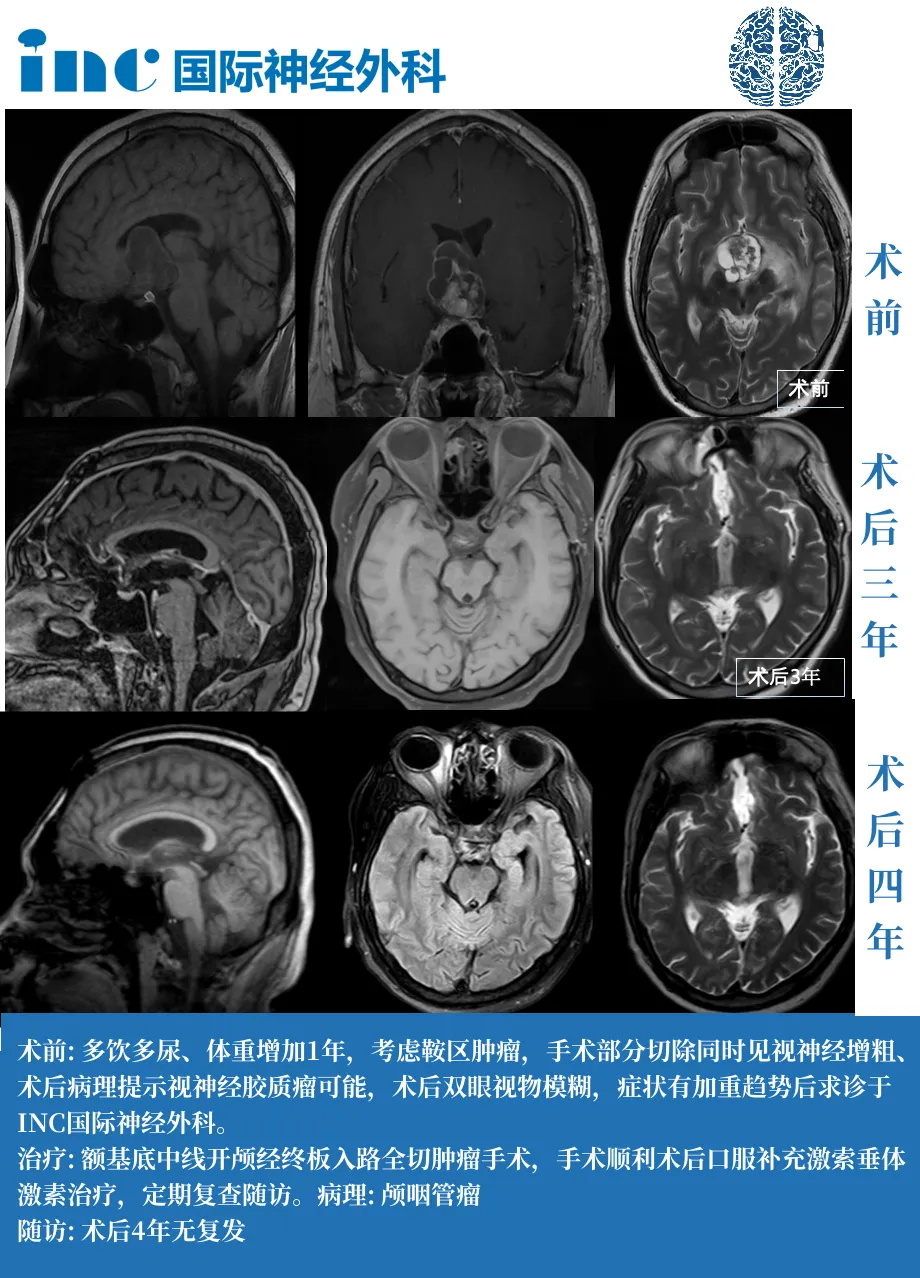

35岁男性——成功全切,术后4年没有复发

点击阅读完整案例:变胖可能不只是嘴馋、爱喝水可能是「颅咽管瘤的警报」